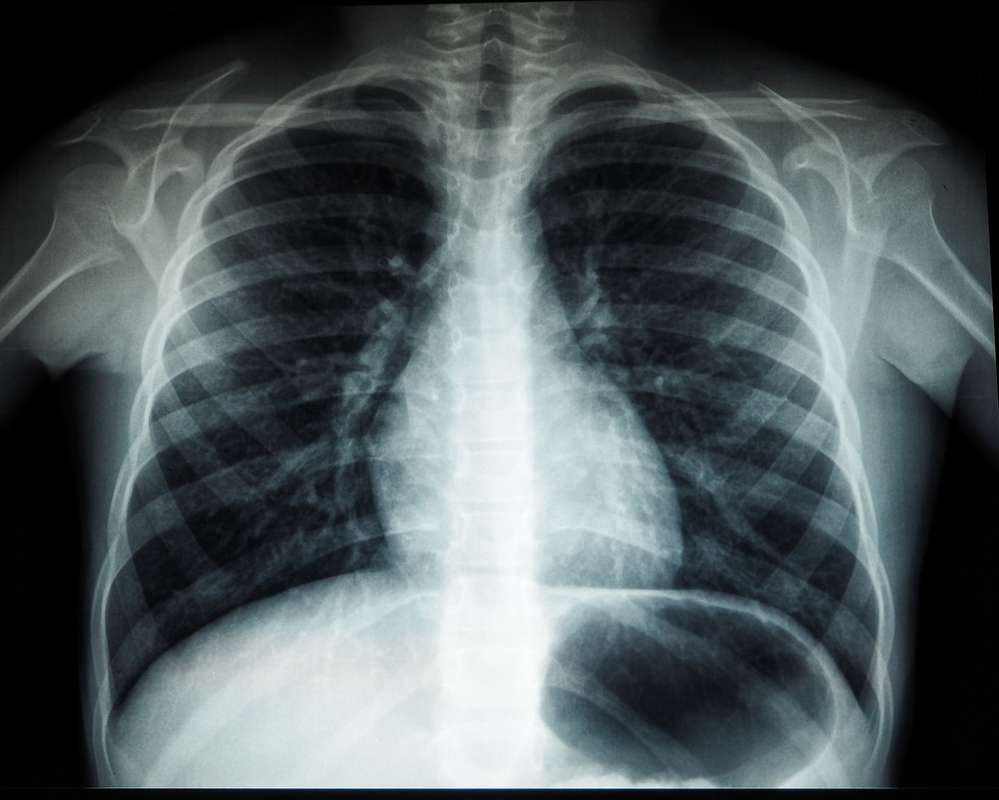

According to an article on NBC.com, Mycoplasma pneumonia has broken out in Ohio with several cases reported in Denmark and China. This respiratory illness is caused by a bacteria.